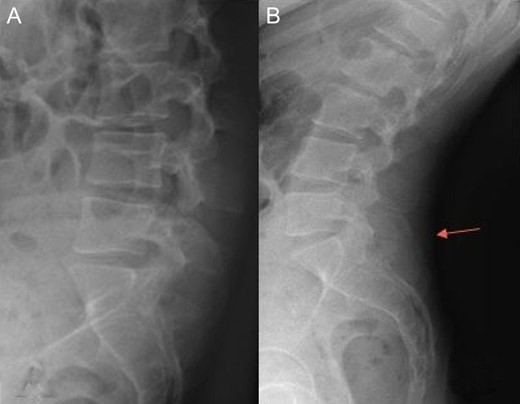

Radiography of the spine revealed an asymmetry of pelvis (Fig. 1), and despite a report refuting Baastrup’s disease, we can see a contact between spinous processes of L5 and S1 in extension (Fig. 2).

Radiography of lumbar spine (A: flexion, B: extension). We can see a contact between spinous processes of L5 and S1 (arrow).